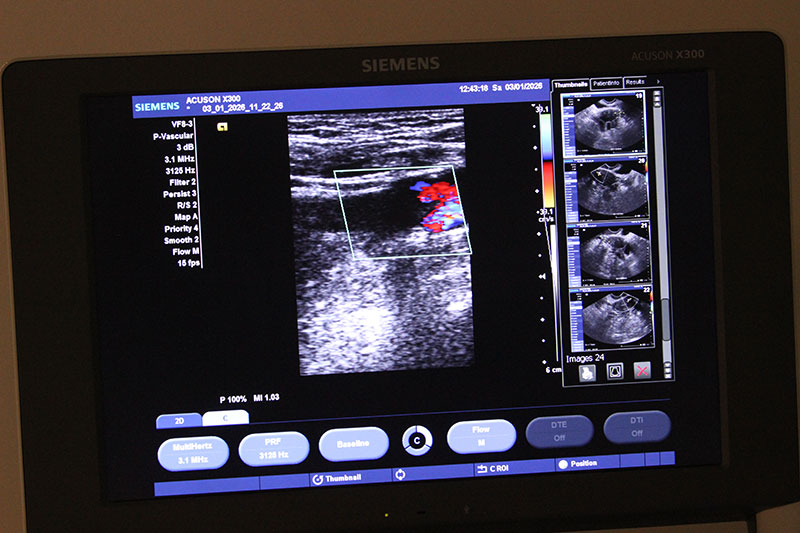

В основе метода лежит принцип эхолокации. Специальный датчик испускает ультразвуковые колебания, которые по-разному отражаются от тканей в зависимости от структуры. Принятые сигналы обрабатываются и формируют компьютерное изображение на мониторе в режиме реального времени. Ультразвук можно применять неоднократно для динамического контроля изменений.

В медицинском центре доктора Бегмы УЗИ проводят опытные врачи-диагносты, что гарантирует надежные результаты для дальнейшего лечения. Наша клиника располагает передовым оборудованием экспертного уровня. Это позволяет обнаруживать заболевания на начальных этапах: от новообразований, проблем с кровообращением до воспалений. Обследование длится от 15 до 40 минут и не требует пребывания в стационаре.